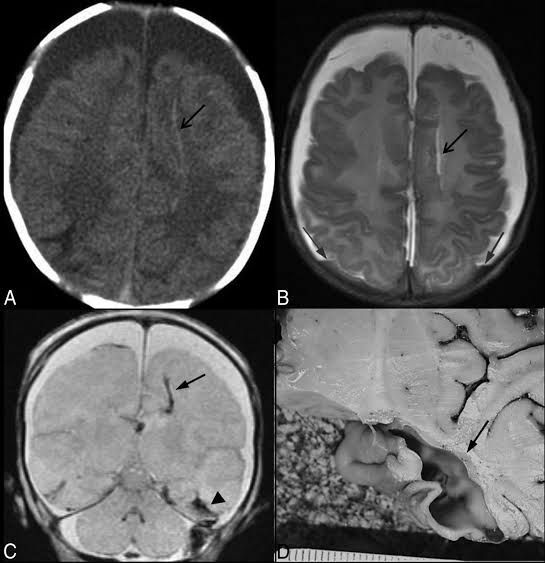

A chronic subdural hematoma (SDH) is a collection of blood on the brain’s surface, under the outer covering of the brain (dura). It usually begins forming several days or weeks after bleeding initially starts. Bleeding is usually due to a head injury. A chronic SDH doesn’t always produce symptoms. When it does, it generally requires surgical treatment.